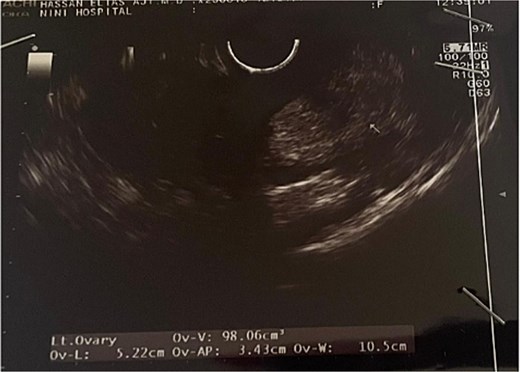

Transvaginal ultrasound revealed a well-circumscribed, heterogeneous uterine mass with mixed echogenicity (Figs 1 and 2). Given the imaging characteristics, a malignant uterine neoplasm, particularly sarcoma, was initially suspected.